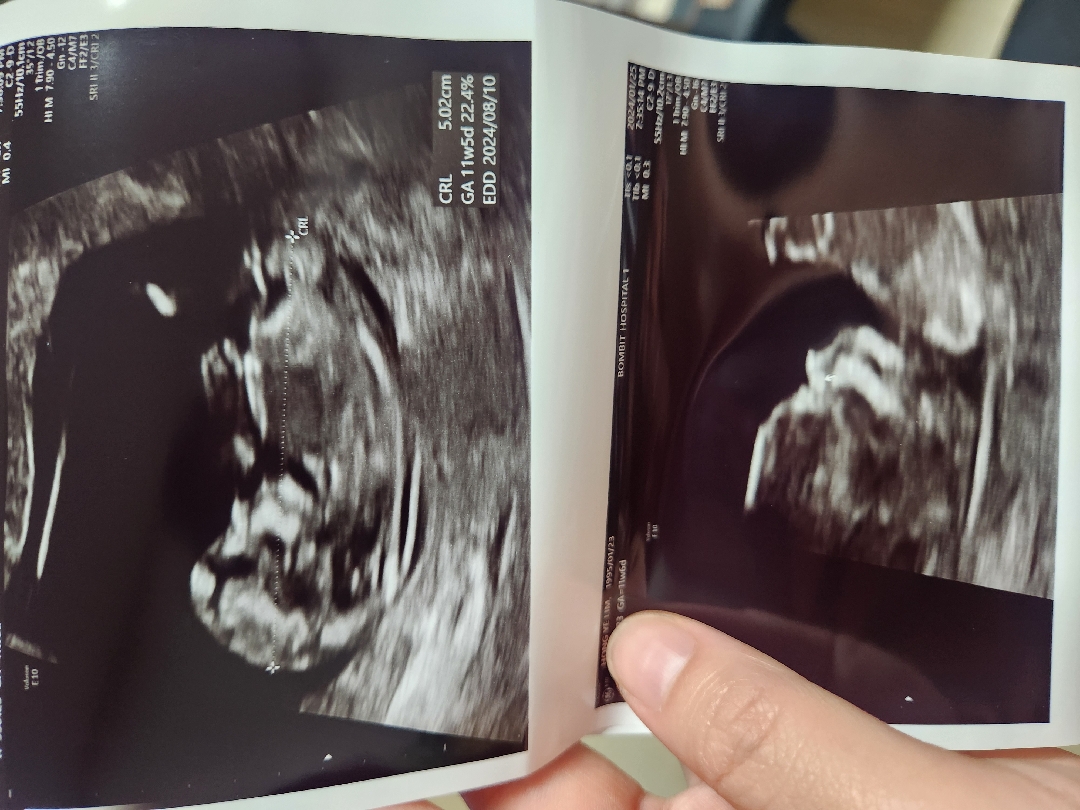

각도법! 성별 ! 넘 궁금해요👉🏻👈🏻

성별 상관없지만 1차 검사하고 오니 궁금해서 올려보아요 고수님들 촘파 어떻게 보이실까요?🙈

저는 딸로 보여요🩵